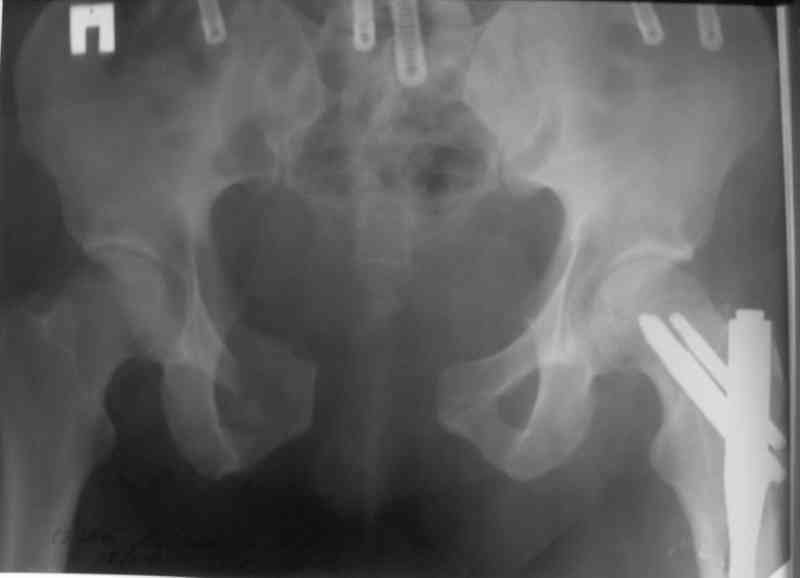

Бедро фиксировал длинной DCS.

По типу бриджинг плэйтин, крюком удалось низвести малый вертел и фиксировать винтом для восстановления медиальной стенки.

Я помню технику транссакральной фиксации тазового кольца длинными 5 мм Шанцами - повреждения типа В, в этом же случае задний отдел тоже вовлечен

т.е комбинированная нестабильность, поэтому вопрос - достаточно ли только двух Шанцев для стабилизации таза? Что вы думаете об anterior Right SI joint plating + tension band plating from the back.?

PS после фиксации бедра под Эопом посмотрел инлет и аутлет проекции, насколько репонируемо смещение правой половины таза *невооруженными*

руками - никаких шансов улучшить позицию иначе бы конечно воспользовался длинными Шанцами сразу после бедра.

В приложении отправляю послеопер. снимки бедра и лодыжки обсуждаемого вчера больного.

В приложении послеоперационные картинки.